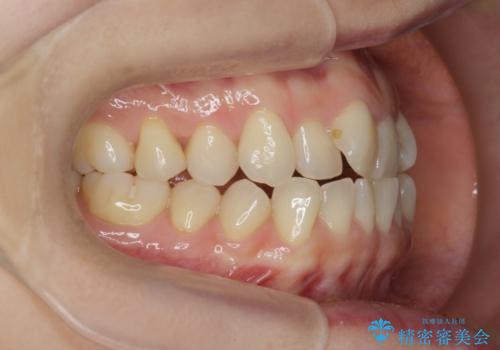

前歯の目立つガタつきをマウスピース矯正で治療

- 大きく傾いてしまった前歯のガタつきの改善を求めて来院されました。

前歯のガタつきをしっかりと取り、機能的・審美的に理想的な歯並びをマウスピース矯正で達成します。

強度のガタつきはマウスピース単体では並び切ることが難しいこともありますが、しっかりと装着していただいたことで良好な治療結果を得ることができました。